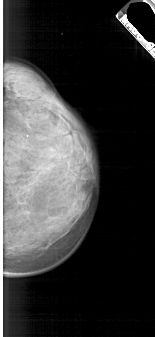

A_1874_1.RIGHT_CC

RIGHT_CC LINES 4711 PIXELS_PER_LINE 2161 BITS_PER_PIXEL 12 RESOLUTION 43.5 NON_OVERLAY